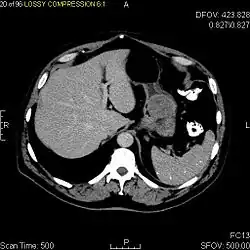

Large GISTs

As the tumor grows it may project outside the bowel (exophytic growth) and/or inside the bowel (intraluminal growth), but they most commonly grow exophytically such that the bulk of the tumor projects into the abdominal cavity. If the tumor outstrips its blood supply, it can necrose internally, creating a central fluid-filled cavity with bleeding and cavitations that can eventually ulcerate and communicate into the lumen of the bowel. In that case, barium swallow may show an air, air-fluid levels or oral contrast media accumulation within these areas.[21][25] Mucosal ulcerations may also be present. In contrast-enhanced CT images, large GISTs appear as heterogeneous masses due to areas of living tumor cells surrounding bleeding, necrosis or cysts, which is radiographically seen as a peripheral enhancement pattern with a low attenuation center.[20] In MRI studies, the degree of necrosis and bleeding affects the signal intensity pattern. Areas of bleeding within the tumor will vary its signal intensity depending on how long ago the bleeding occurred. The solid portions of the tumor are typically low signal intensity on T1-weighted images, are high signal intensity on T2-weighted images and enhanced after administration of gadolinium. Signal-intensity voids are present if there is gas within areas of necrotic tumor.[22][26][27]

Features of malignancy

Malignancy is characterized by local invasion and metastases, usually to the liver, omentum and peritoneum. However, cases of metastases to bone, pleura, lungs and retroperitoneum have been seen. In distinction to gastric adenocarcinoma or gastric/small bowel lymphoma, malignant lymphadenopathy (swollen lymph nodes) is uncommon (<10%) and thus imaging usually shows absence of lymph node enlargement.[20] If metastases are not present, other radiologic features suggesting malignancy include: size (>5 cm), heterogeneous enhancement after contrast administration, and ulcerations.[4][20][28] Also, overtly malignant behavior (in distinction to malignant potential of lesser degree) is less commonly seen in gastric tumors, with a ratio of behaviorally benign to overtly malignant of 3-5:1.[4] Even if radiographic malignant features are present, these findings may also represent other tumors and definitive diagnosis must be made immunochemically.